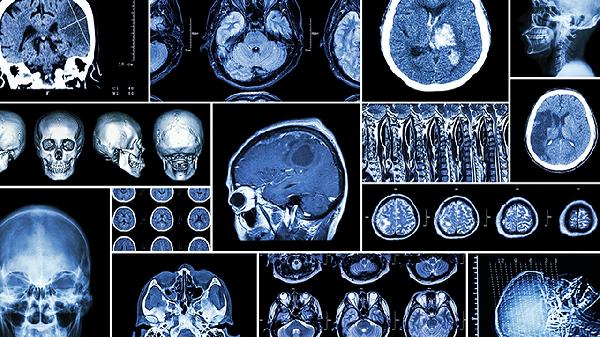

脑梗死脑栓塞是不是同一个概念

脑梗死和脑栓塞不是同一个概念,但存在关联。脑梗死是脑部血液供应中断导致的脑组织坏死,脑栓塞是血管被血栓或异物堵塞。治疗需根据具体病因,包括溶栓、抗凝和手术干预等。

1、脑梗死是指脑部血液供应中断导致的局部脑组织坏死。原因可能包括动脉粥样硬化、血管痉挛或血液高凝状态。治疗方式包括静脉溶栓治疗、抗血小板药物如阿司匹林和改善脑循环药物如尼莫地平。

2、脑栓塞是指血管被血栓、脂肪滴或其他异物堵塞,导致血液无法正常流动。常见原因有心房颤动、心脏瓣膜病或动脉硬化。治疗手段包括抗凝治疗如华法林、溶栓治疗如阿替普酶和手术取栓。

3、脑梗死和脑栓塞在发病机制上有所不同,但最终都会导致脑组织缺血缺氧。预防措施包括控制高血压、糖尿病和血脂异常,以及戒烟限酒。康复治疗包括物理治疗、语言训练和心理支持。

脑梗死和脑栓塞虽然不同,但都需要及时诊断和治疗,以最大限度地减少脑损伤和后遗症。通过综合治疗和预防措施,可以显著降低发病风险和改善预后。